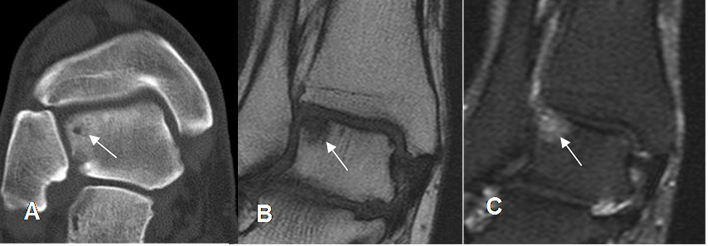

Fig 89. Pinzamiento anterior.

Rx lateral. Formación de osteofitos en la parte anterior de la tibia y el borde superior del talo.

Fig 90. Pinzamiento anterior.

A: RM sagital en T2. Formación de osteofitos.

B: RM axial en T2. Derrame articular en la parte anterior de la articulación, con sinovitis asociada. (Flecha).